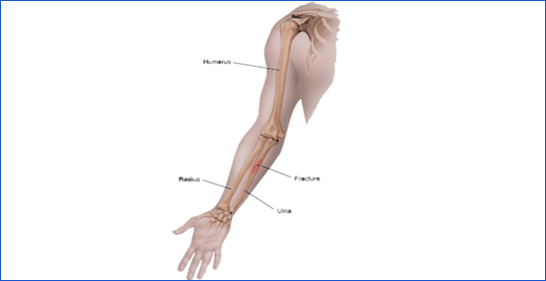

5. Forearm Fracture

A break in either the radius or ulna bones of the forearm.

Icon Cause: Falls, sports injuries, or direct impact.

Icon Symptoms: Swelling, deformity, and pain with wrist or elbow movement.

Icon Treatment: Casting for minor fractures, surgery for severe cases.